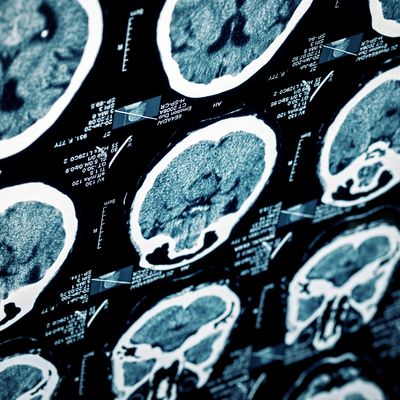

Brain Injury Assessments

Comprehensive Brain Injury Assessments to Understand Cognitive and Emotional Changes

Brain injuries, including those caused by stroke, traumatic brain injury (TBI), or acquired brain injury (ABI), can affect different parts of the brain and lead to changes in thinking, memory, emotions, and behaviour. Our assessments aim to provide a detailed understanding of how your brain injury may be impacting your daily life.

Conducted by a multidisciplinary team, we use a variety of reliable tools to assess cognitive functions such as memory, attention, executive skills, and mood. This includes tests like the Wechsler Memory Scale and assessments of anxiety and depression. We also consider your premorbid functioning to understand changes since the injury.